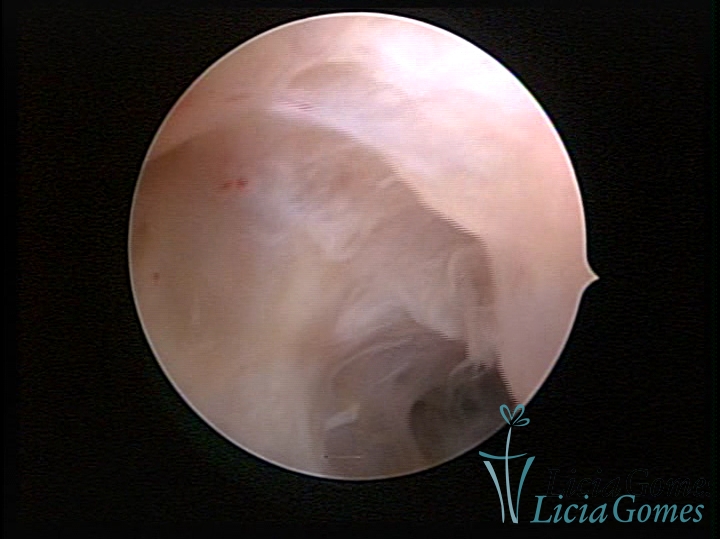

SINÉQUIA TIPO MUCOSA